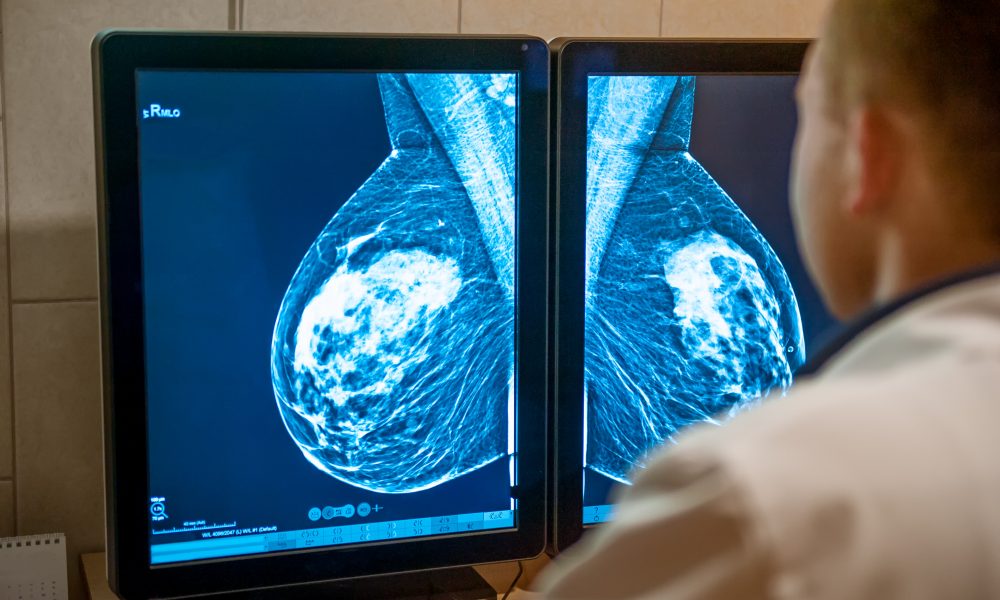

“Promising” breast cancer treatment may save 10,000 lives a year

A “promising” immunotherapy drug can cut the risk of triple-negative breast cancer by more than a third, a recent long-term global study has found.

Triple-negative breast cancer is very aggressive and has a much poorer prognosis than other types of the disease.